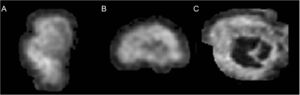

Publication: PLoS One. 2018 Nov 7;13(11):e0207163. PMID: 30403747 | PDF Authors: Asami T, Nakamura R, Takaishi M, Yoshida H, Yoshimi A, Whitford TJ, Hirayasu Y. Institution: Department of Psychiatry, Graduate School of Medicine, Yokohama City University, Yokohama, Japan. Abstract: The amygdala plays an important functional role in fear and anxiety. Abnormalities in the amygdala are believed to be involved in the neurobiological basis of panic disorder (PD). Previous structural neuroimaging studies have found global volumetric and morphological abnormalities in the amygdala in patients with PD. Very few studies, however, have explored for structural abnormalities in various amygdala sub-regions, which consist of various sub-nuclei, each with different functions. This study aimed to evaluate for volumetric abnormalities in the amygdala sub-nuclei, in order to provide a better understanding neurobiological basis of PD. Thirty-eight patients with PD and 38 matched healthy control (HC) participants underwent structural MRI scanning. The volume of the whole amygdala, as well as its consistent sub-nuclei, were calculated using FreeSurfer software. Relative volumes of these amygdala sub-regions were compared between the two groups. Results showed significantly smaller volumes in the right lateral and basal nuclei in the patients with PD compared with the HC. Lateral and basal nuclei are thought to play crucial role for processing sensory information related with anxiety and fear. Our results suggest that these particular amygdala sub-regions play a role in the development of PD symptoms. Funding:

Nuclei of the amygdala. a) 3D image was constructed using 3D Slicer. b) Coronal images of the nuclei in the right amygdala. |